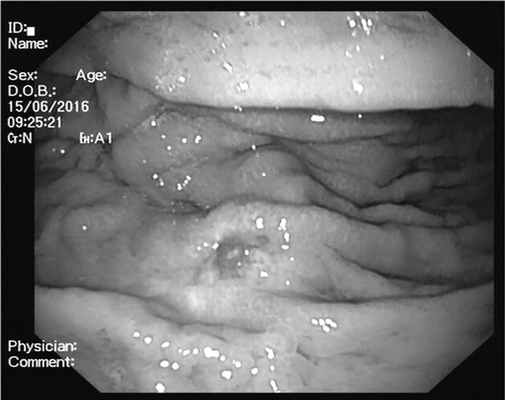

Больной обратился в МНИОИ им. П.А. Герцена. Учитывая неэффективность ранее проведенного лечения, диагноз диффузной В-клеточной крупноклеточной лимфомы подвергся сомнению. С целью верификации опухоли выполнено дообследование. При ЭГДС на границе верхней и средней трети желудка по большой кривизне и передней стенке сохраняется зона опухолевой инфильтрации размером 4×5 см, стенка желудка в этой области каменистой плотности, перистальтика в данной зоне не прослеживается. В центре данной зоны выявлены 2 площадки размером до 1 см, лишенные складок (рис. 3). Рис. 3. Эзофагогастродуоденоскопия. При осмотре в режиме NBI HD слизистая оболочка в данной области лишена архитектоники ямок, визуализируются патологически извитые расширенные капиллярные петли.